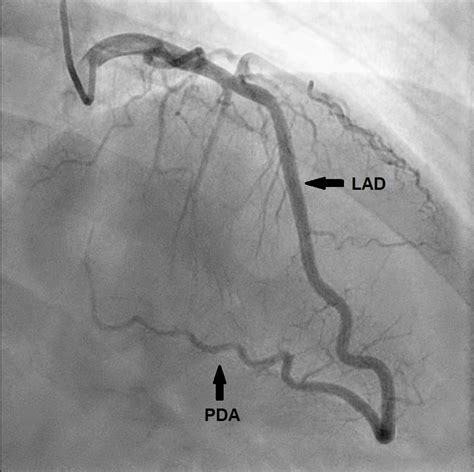

• Coronary Angiography: This invasive procedure involves inserting a catheter into the coronary arteries to visualize the blood flow and identify any blockages or narrowing.

• Imaging Techniques: Advances in imaging technologies, such as cardiac MRI and CT angiography, are improving the visualization of the Posterior Descending Artery and other coronary arteries. This allows for more accurate diagnosis and treatment planning.